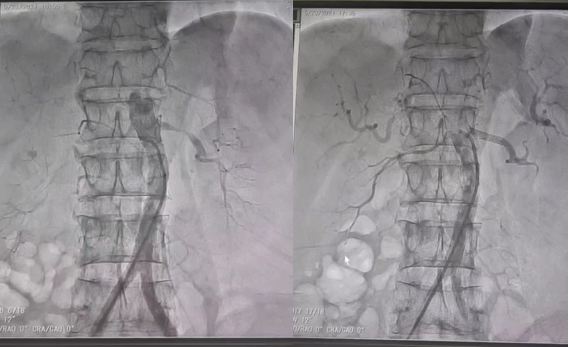

患者系中年男性,自觉乏力伴头晕于黑料网西咸院区肾内科就诊。王琼主治医师在诊查中发现患者肾功能中度损伤伴高血压及高钾血症,血压高达180/90mmhg,肾脏超声提示左肾动脉起始段明显纤细。考虑到左肾动脉局部明显狭窄,严重影响肾灌注及功能,但行传统的外科手术治疗创伤大,恢复慢,患者接受度低,结合患者情况,闫晓辉副主任医师和微创介入科陈思攀主任详细评估病情后,为患者制定了安全、有效的微创手术方式,即“左肾动脉造影及成形术”。医患双方充分沟通,并取得患者及家属的同意后,手术由微创介入科团队完成。在进行了多角度肾动脉造影后,精准测量左肾动脉狭窄段的长度、形态等参数,通过纤细导管将肾动脉专用支架送入肾动脉狭窄段,再次造影确认肾动脉狭窄段消失,血流明显恢复通畅,手术顺利结束。患者安返病房。